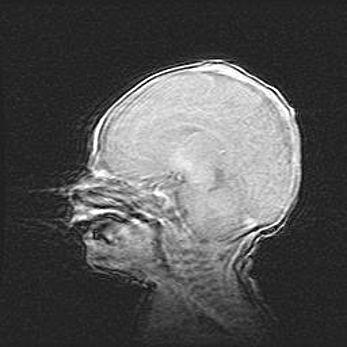

Сообщающаяся гидроцефалия. Кистозная энцефаломаляция головного мозга.

Возраст: 3 месяца 4 дня

Вес: 3100 г

Пол: женский

Окружность головы: 34 см

Срок гестации: 31 неделя

Кистозная энцефаломаляция головного мозга - одна из форм поражения головного мозга в детском возрасте. Характеризуется возникновением множественных и распространённых кист в коре, белом веществе и подкорковых образованиях головного мозга у плодов, новорождённых и детей раннего возраста. Развитие кистозной энцефаломаляции связано с внутриутробной асфиксией и гипотонией, родовой травмой, тромбозом синусов, пороками развития сосудов, инфекциями, сепсисом и другими причинами. Наиболее значимые инфекционные агенты: вирусы простого герпеса, цитомегалии, краснухи, токсоплазмы, энтеробактерии, золотистый стафилококк и другие.